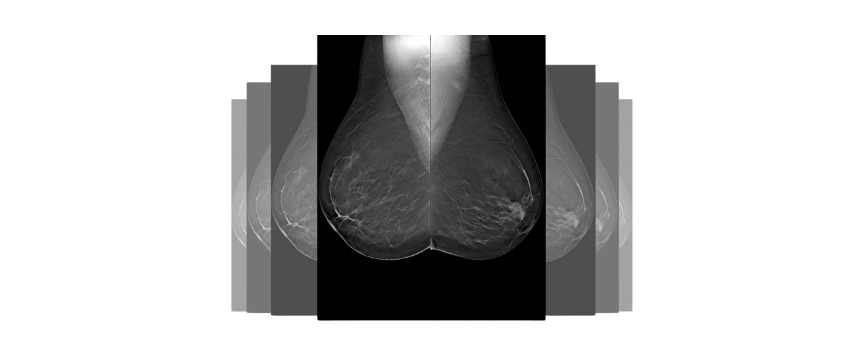

Obrazy Kliniczne Planmed Clarity 3D